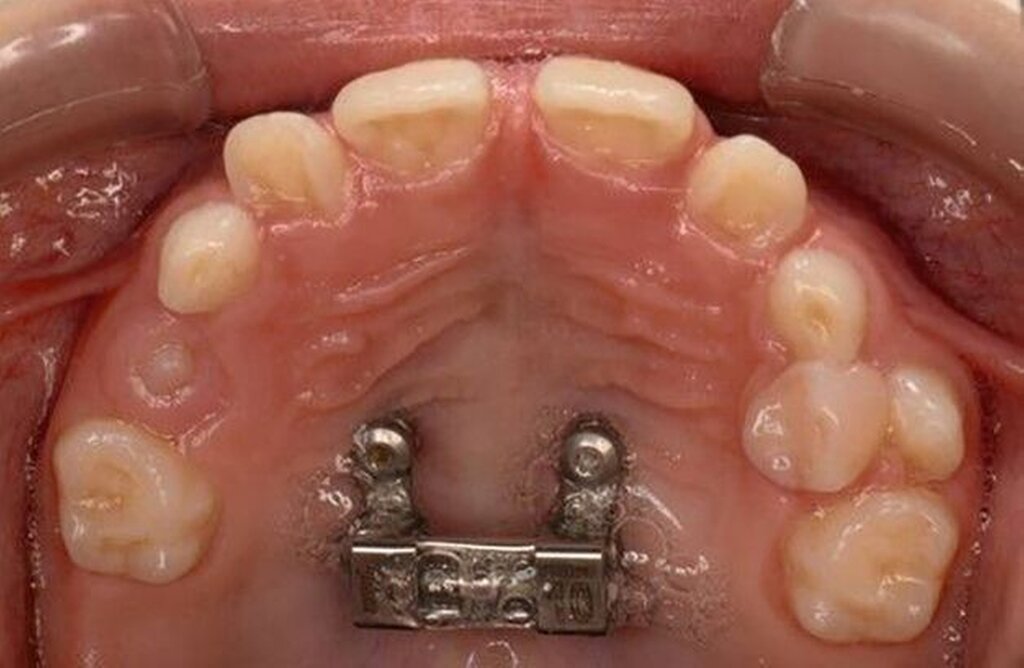

Die Zähne 36, 37, 46 und 47 wurden in Allgemeinanästhesie chirurgisch freigelegt. Zusätzlich wurden die beiden paramedianen Mini-Implantate (2 x 9 mm, Benefit System; PSM North America, Indio, CA) ohne Vorbohren mithilfe der zuvor hergestellten Schablone inseriert (Abbildung 3). Für die Platzierung der Mini-Implantate wurde ein Winkelschraubendreher verwendet. Direkt nach der Operation wurde die bmx DIRECT Hyrax-Schraube (10 mm, BENEfit®-System, Dentalline, Birkenfeld, Deutschland) an den Mini-Implantaten befestigt, um ein MARPE zu erzielen (Abbildung 4).